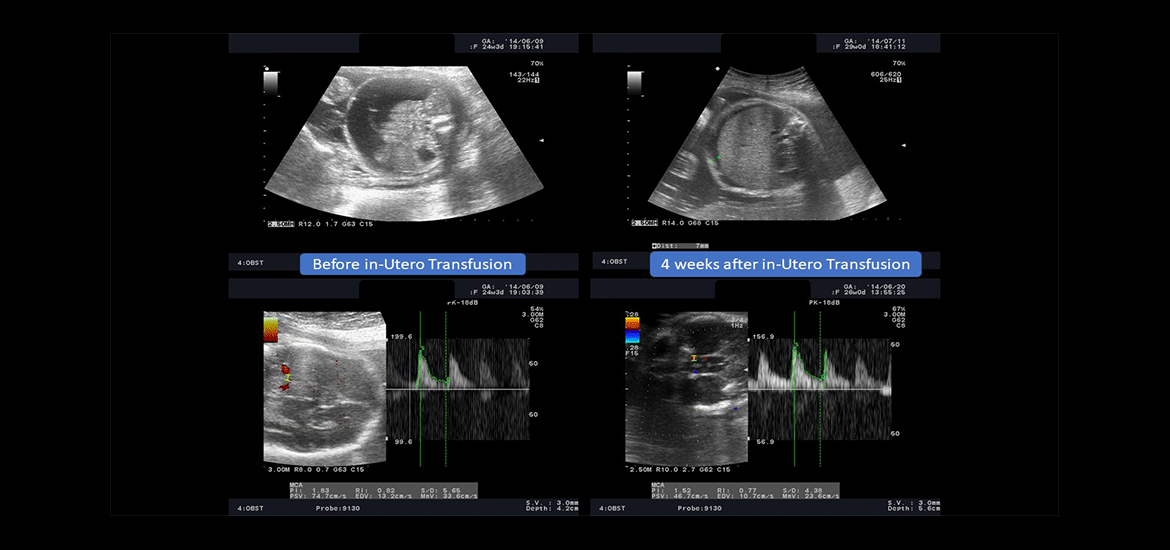

Dr Abi Nader’s main research interests relate to fetal medicine and female urinary incontinence.